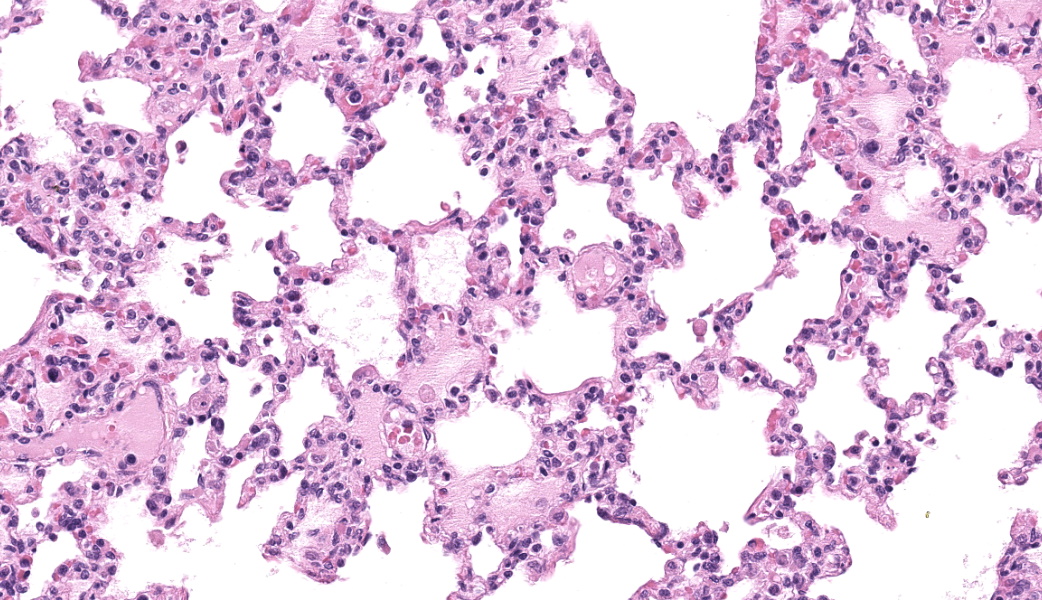

Alveolar septa are mildly thickened and hypercellular, and contain increased numbers of macrophages, rare neutrophils, and small quantities of fibrin (occasionally suspicious for capillary fibrin thrombi). Alveolar lumens contain increased numbers of free-floating macrophages, very rare neutrophils, and protein-rich fluid. Most intravascular erythrocytes contain small (1-3 micron) intracytoplasmic basophilic bodies, most visible in alveolar capillaries around the periphery of the histologic sections. Giemsa stains accentuate these small round faintly vacuolated organisms within erythrocytes.Contributor's Morphologic Diagnoses:

Generalized histiocytic and neutrophilic alveolitis with multifocal capillary thrombosis and intravascular, intraerythrocytic parasites (Babesia vogeli)Contributor's Comment:

Lung: Pneumonia, interstitial, histiocytic and neutrophilic, subacute, diffuse, moderate, with intraerythrocytic piroplasms.JPC Comment:

MAJ Fiddes chose this case specifically because it was going to be a diagnostic challenge. The intraerythrocytic piroplasms of Babesia sp. are quite difficult to see until you find one and got an eye for them within erythrocytes; then, they were much easier to spot. A few participants were successful in finding these small parasite. Along with discussion on the basics and life cycle of Babesia sp., which the contributor’s comment beautifully covers, conference goers participated in a matching game of other boards-worthy infectious hemotropic agents of note. These agents and their matching facts included Anaplasma sp., which may infect platelets, Theileria sp., which infect leukocytes and are another genus of piroplasm, Mycoplasma sp., which tend to reside in an epicellular location, and Cytauxzoon felis, yet another piroplasmid and one that has a bobcat reservoir host.Babesia sp. are apicomplexan piroplasmid protozoans that infect erythrocytes in numerous species, ultimately lysing infected red blood cells (RBCs) and resulting in intravascular hemolysis within the host. As mentioned, by the contributor, there are several species of Babesia that infect dogs, and there is a wide range of severity in the clinical manifestations amongst these. The focus here will primarily be on Babesia canis, which infects dogs, and Babesia bovis, the species responsible for most Babesia infections in cattle and has a substantial amount of research behind it.